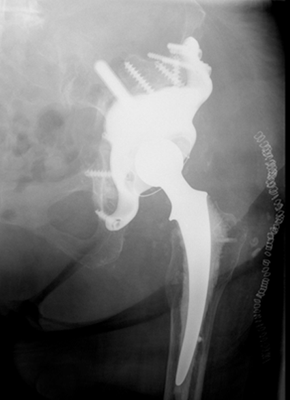

Case Studies

With more than 40,000 individual solutions during the last 50 years, we have been able to gain a lot of experience in this field. We already provided successful solutions for nearly every anatomical region of the human body. See some of our case studies below…